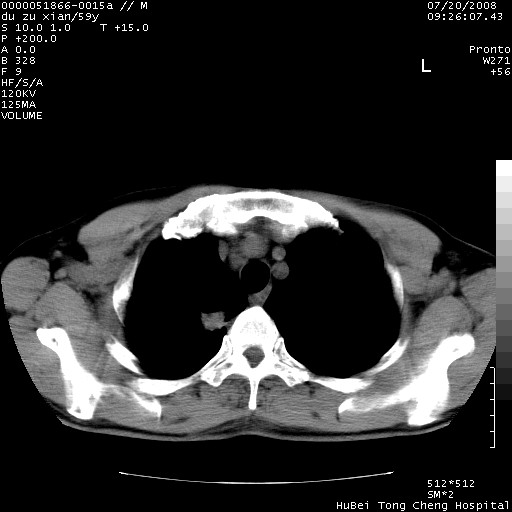

以下是引用宇宙ct在2008-8-25 23:21:00的发言:[br]右肺周围性肺癌并肋骨转移,纵隔淋巴结转移。

以下是引用zsl6918在2008-8-25 22:40:00的发言:[br]右肺周围性肺癌并肋骨转移,纵隔淋巴结转移。

以下是引用zy_zj在2008-8-26 15:24:00的发言:[br]单从病变本身,我倾向良性炎性病变,但肋骨转移了,所以说是考虑右肺周围性肺癌并肋骨、纵隔淋巴结转移可能性大。